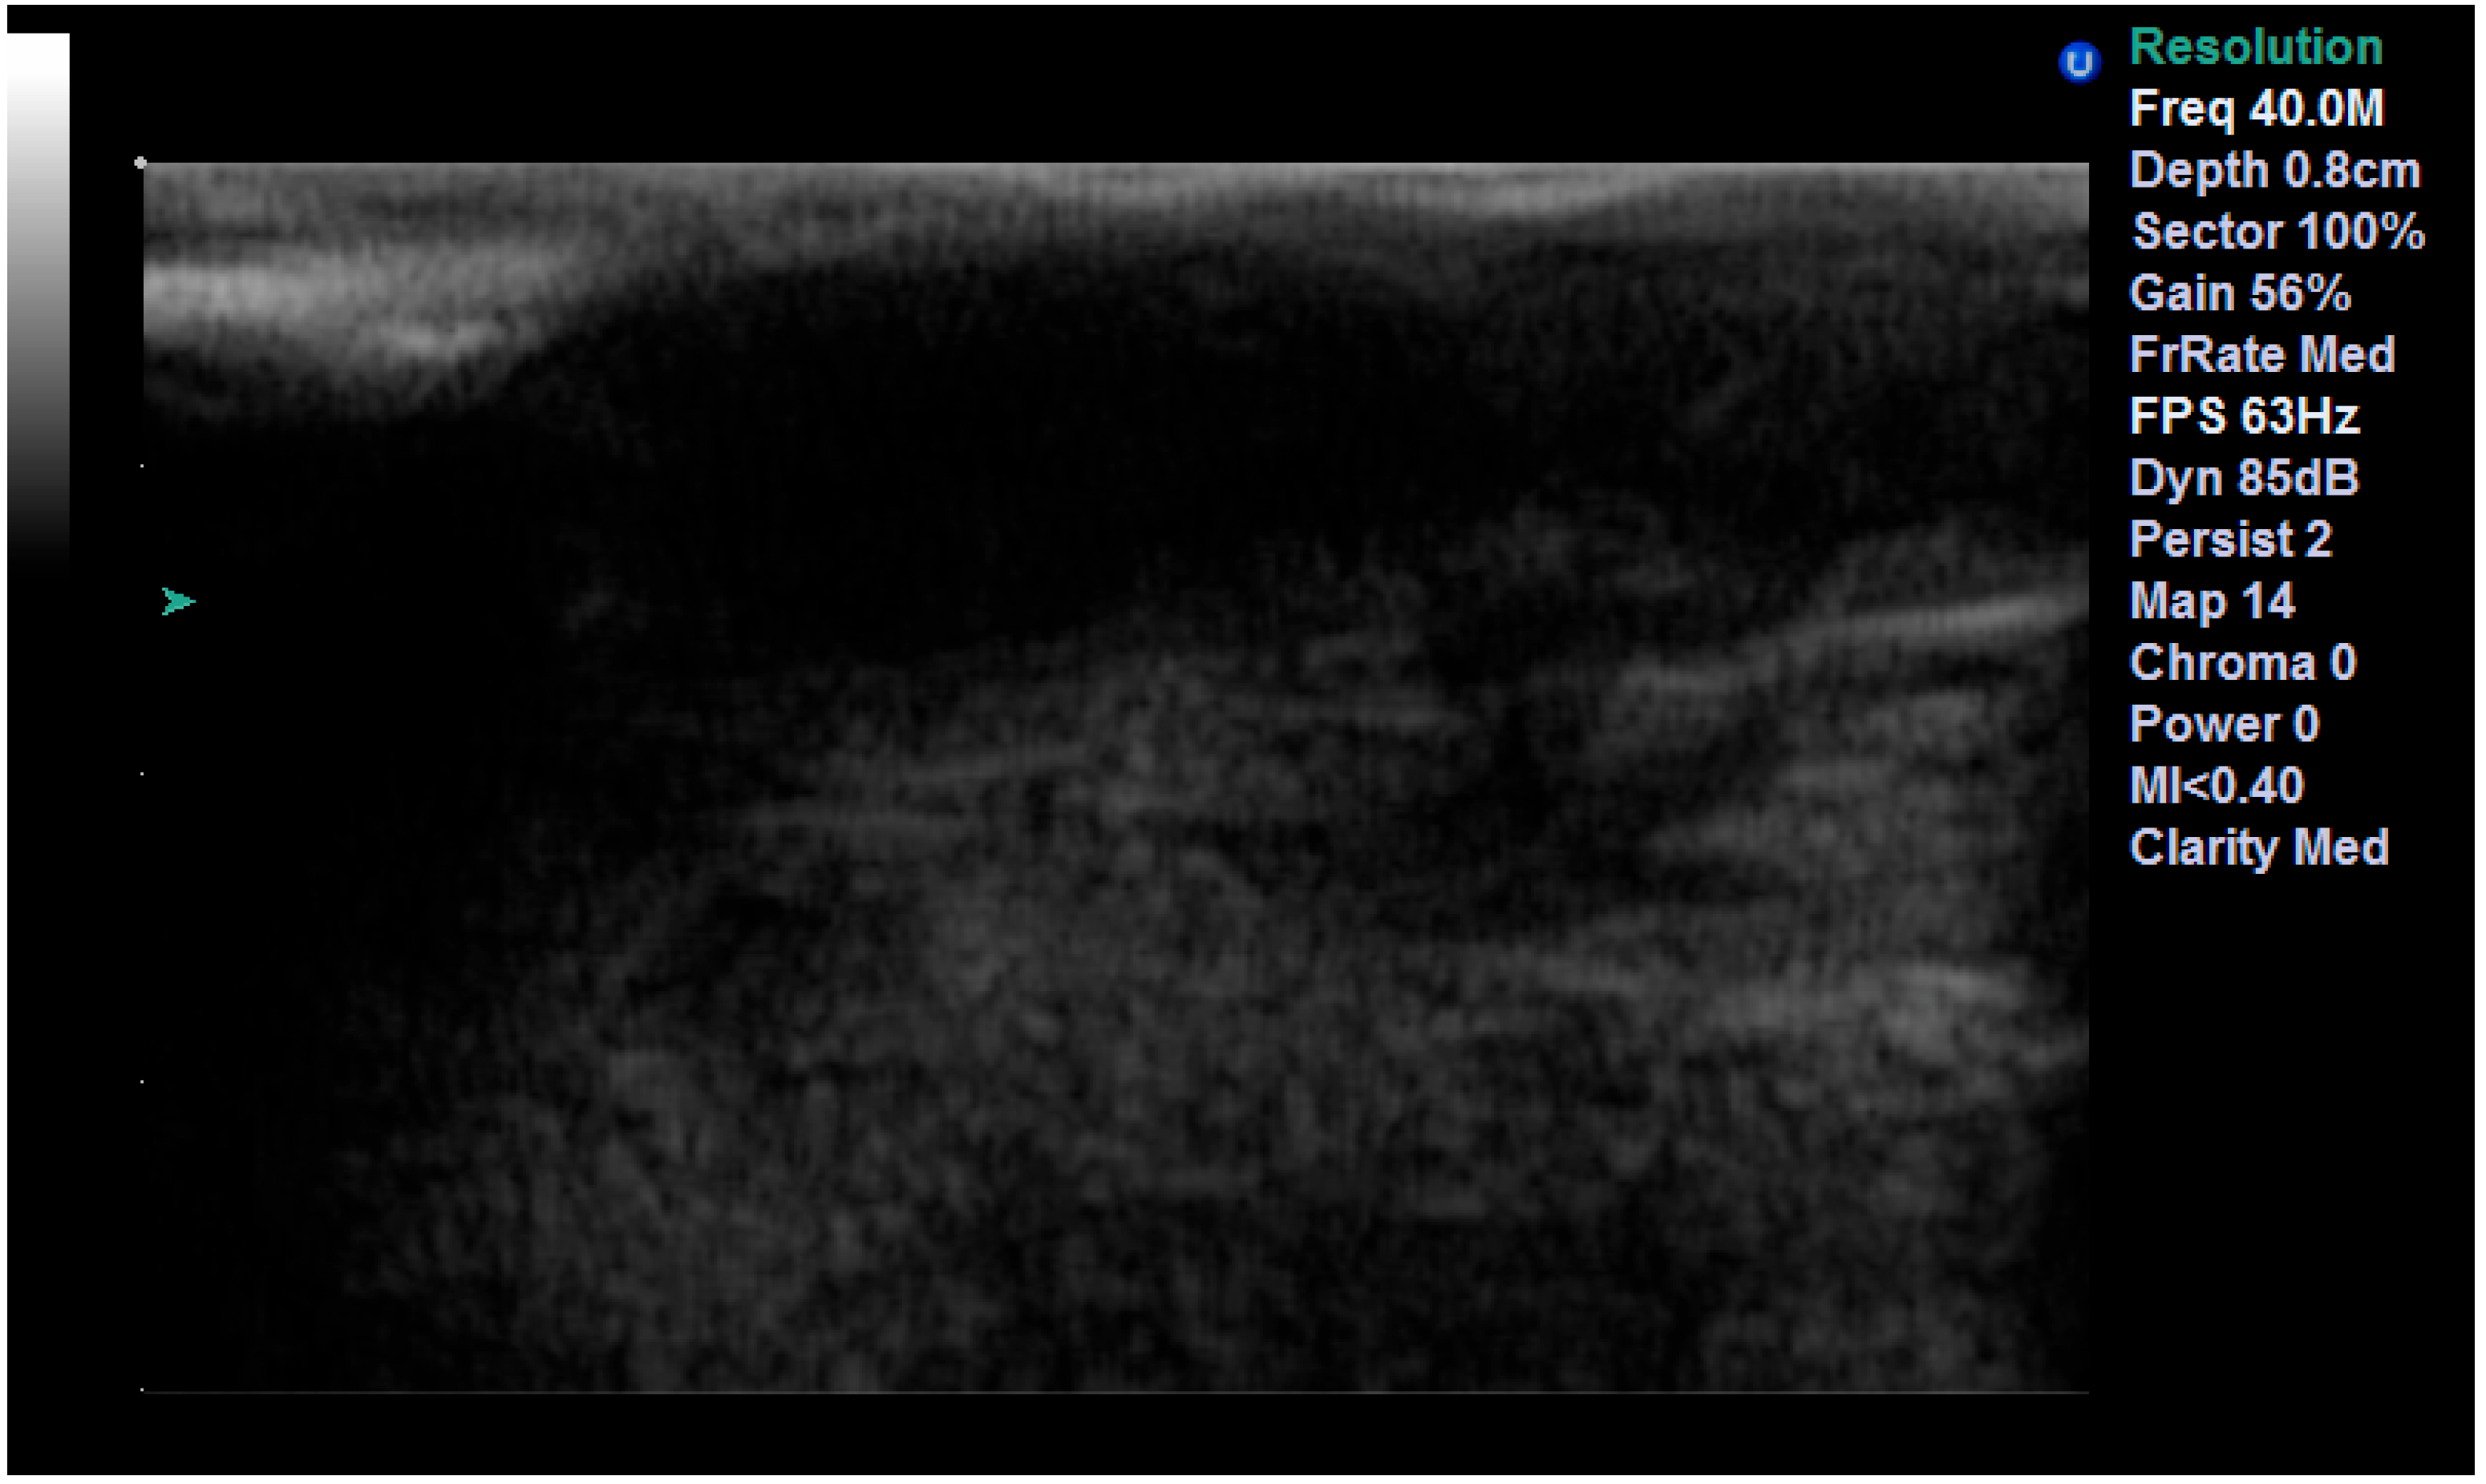

We found a very high correlation between the ultrasound measurement of the surgical margins and pathological reports, with the best result being achieved with the 13 MHz transducer, followed by the 20 MHz and 40 MHz transducers (Figure 8) (Table 5).

Figure 8.

Surgical margins measurement by US and histopathology.

Regarding the role of US in the treatment of NMSC, few studies concluded that US can easily detect malignant involvement of the margins. This may play a role in the treatment of skin cancer and prevention of local recurrence, providing improved overall survival rates. The adjacent normal tissue is measured from the limit of the tumor to the surgical resection margin. It can be easily measured on grayscale examination or elastography [44,45]. Our findings regarding the evaluation of surgical margins postoperatively illustrate the utility of this technique for immediate measurement of surgical margins directly in the operating room. All three transducers (13, 20 and 40 MHz) have shown very good results, but the most accurate was the 13 MHz transducer. This can be explained by how the lower the frequency, the deeper or greater penetrance a sound wave has. If positive or close margins are visualized, the surgery can be completed immediately. This way, the surgeon can avoid insufficient resection of the tumor or unnecessary sacrifice of healthy tissue. All these should reduce the recurrence rate and improve overall survival, but further studies are necessary to ascertain this fact.